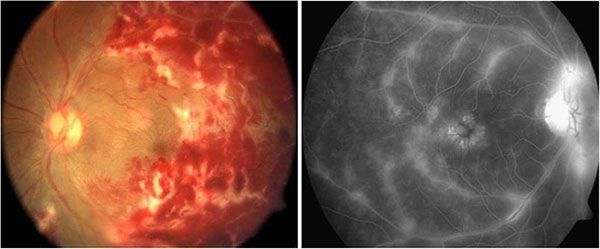

2. Xuất huyết dịch kính là bệnh gì?

Xuất huyết dịch kính là hiện tượng máu chảy vào khoang chứa dịch kính của mắt, khi đó máu hòa chung với dịch kính. Nếu không được phát hiện, điều trị đúng phác đồ khi bị xuất huyết dịch kính, người bệnh sẽ xuất hiện các triệu chứng dấu hiệu ruồi bay trước mắt, thấy màu hồng và thị lực giảm đi nhanh chóng. Theo thống kê, tỷ lệ người mắc xuất huyết dịch kính là 7/100.000.